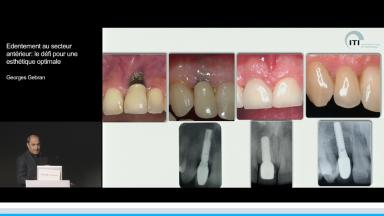

Edentement au secteur anterieur: le défi pour une esthetique optimale

Georges Wadih Gebran

A partir de la description des facteurs de risque esthétique du bloc incisivo-canin maxillaire, de la présence d’os et de gencive autour des implants, le conférencier présente une succession de cas cliniques décrivant ses procédures chirurgicales et prothétiques.